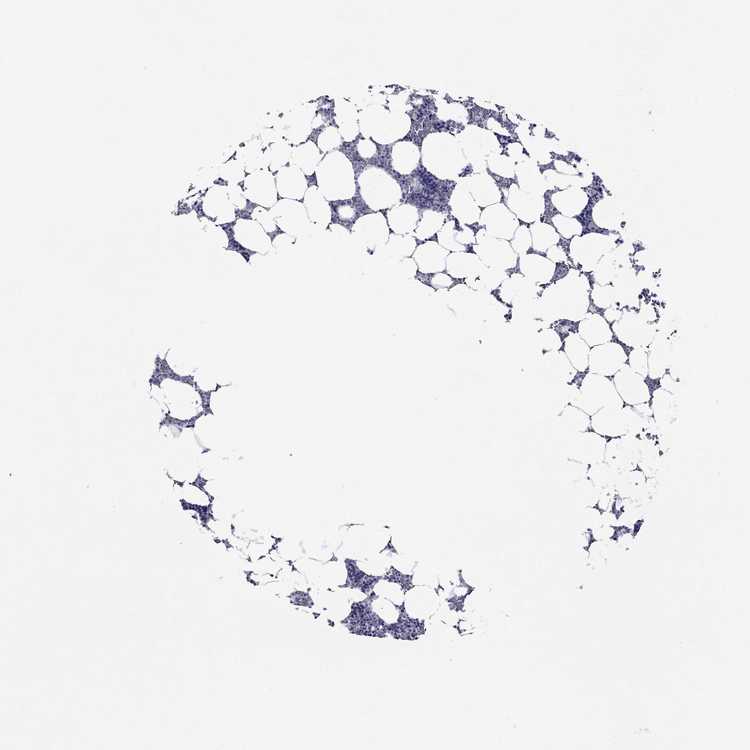

TISSUE PRIMARY DATA BONE MARROW Show tissue menu

BONE MARROW - Antibody stainingi

Antibody staining in the annotated cell types in the current human tissue is reported as not detected, low, medium, or high, based on conventional immunohistochemistry profiling in selected tissues. This score is based on the combination of the staining intensity and fraction of stained cells.

Each image is clickable and will lead to virtual microscopy that enables deeper exploration of all samples and also displays staining intensity scores, fraction scores and subcellular localization as well as patient and tissue information for each sample.

Antibody HPA055744Antibody HPA061936

Hematopoietic cells Not detectedNot detected